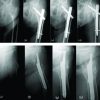

Between 2014 and 2016, three patients of isolated avulsion fractures of lesser trochanter presented to our hospital (Table 1). All three were adolescent males, two were aged 13 years old, and one was 15 years old. Two patients had involvement of left side while running in a school sprinting competition and were unable to complete race while hearing a sudden pop at the time of injury. The other had right side involvement and sustained trauma due to fall from horse. All patients reported immediately to hospital with complaints of pain in groin, limp, and antalgic gait on presentation. General physical examination was unremarkable. There were no swelling or visible external signs of trauma in any patient. Local examination in supine position was done. Attitude of the limb revealed slight flexion and external rotation deformity. No patient could do active straight leg raise. There was tenderness around the groin and medial aspect of the upper thigh. Flexion of hip was painful, and rotations inflexion were more painful than an extension of hip. Distal neurovascular status of the limb was normal in all cases. There were no significant associated injuries in any patient. Radiographs of the pelvis with both hips revealed avulsion fractures of lesser trochanter (Fig. 1). All fractures were displaced <1.5 cm on radiographs. We did not go for further imaging studies as both the diagnosis and displacement were evident on radiographs. All patients were managed conservatively including analgesics and non-weight bearing mobilization with crutches for 2 weeks followed by partial weight bearing as tolerated. Repeat radiographs at 2 weeks revealed no further displacement of the fragment in any patient (Fig. 2). Passive mobilization of hip and muscle strengthening exercises were started once patients were pain-free after 3 weeks. All patients could bear full weight at 6 weeks. At 12 weeks, no patient had any complaint, had resumed activities of daily living, and hip flexion strength was comparable to opposite side.